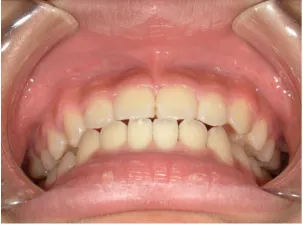

治療前①小1(7y2m):初診

*上顎前歯後方傾斜、上下唇の突出、口唇閉鎖不全傾向、コンケーブなし

| カウンセリング・診断結果 | 骨格的に下顎前方位で下顎骨も大きいタイプで、上の前歯が後ろに傾斜している受け口です。 顔立ちは上下唇が突出していて口唇閉鎖不全傾向がありますが、コンケーブにはなっていません(写真①)。 機能的に低位舌があり、今後受け口を助長する可能性があります。 受け口は、上顎骨の骨格的な前方向の成長を阻害し下顎が前へ強く成長していくため、骨格的な受け口が悪化し永久歯の咬合治療が難しくなり、症例によっては外科的な治療が必要になることがあるため早期に改善し骨格的な悪化を予防する説明をしました。 |